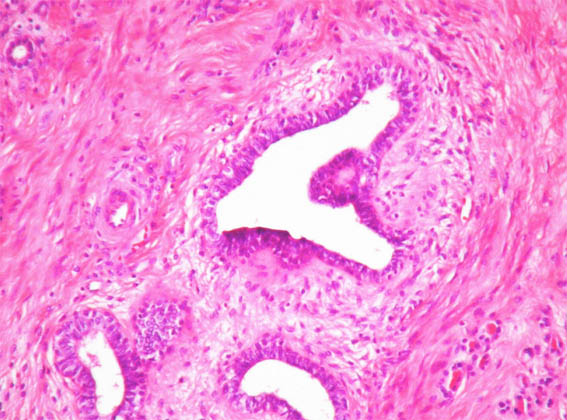

In a 44-year-old woman was incidentally detected, by ultrasound, a renal mass of 3.0 cm of diameter in the upper pole of the left kidney. She had cholelithiasis, with no other clinical alterations. Renal function tests and urinalysis were normal.

Nephrectomy was performed. We receive the case in consultation. See the images:

Figure 4. H&E, X100.